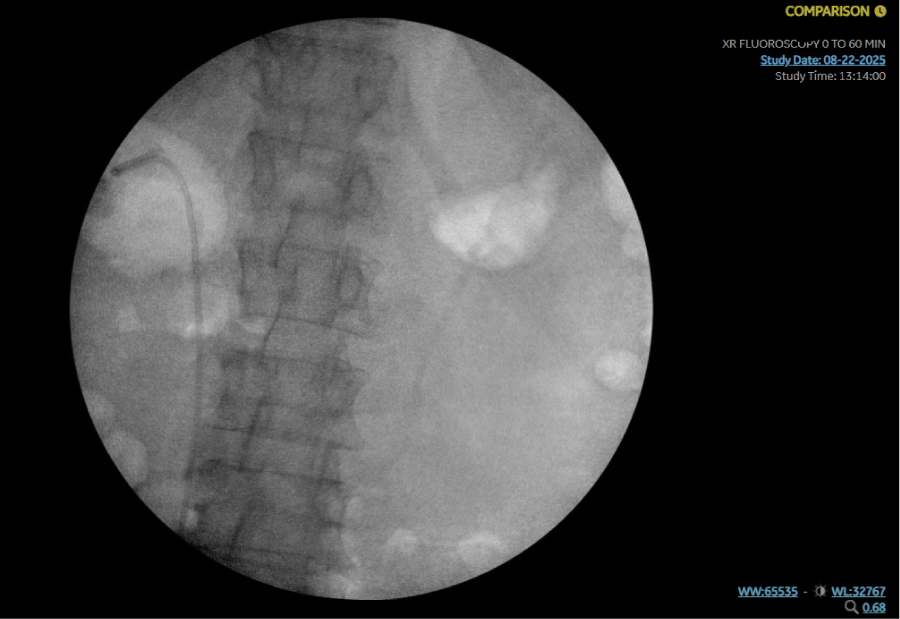

A 64-year-old woman with hypertension and gastroesophageal reflux disease presented with abdominal pain, nausea, vomiting, and fevers for 3 days. On admission, she was tachycardic (HR 110), with blood pressure 133/79 mmHg and temperature 38°C. Laboratory evaluation revealed leukocytosis (WBC 15.5 ×103/µL), lactic acidosis, and thrombocytopenia. Urinalysis was positive for infection with 20 WBC, 10-20 RBCs and Positive Leukocyte Esterase and Nitrites. CT abdomen and pelvis revealed an 8 × 4 mm proximal right ureteral stone with right-sided Uretral Stone and perinephric stranding (Figures 1 and 2).

Figure 1: CT abdomen/pelvis (axial) showing patchy right renal cortical enhancement and perinephric edema consistent with obstructive pyelonephritis. View Figure 1

The patient was started on IV ceftriaxone and fluids. Urology was consulted, Infectious Disease and Nephrology were consulted. Blood cultures grew E. coli (2/2 bottles). Urology performed cystoscopy with ureteral stent placement, confirmed fluoroscopically (Figure 3). Infectious Disease recommended ceftriaxone 2 g IV daily.

Figure 3: Intraoperative fluoroscopy image confirming placement of a right ureteral stent (arrowhead). View Figure 3